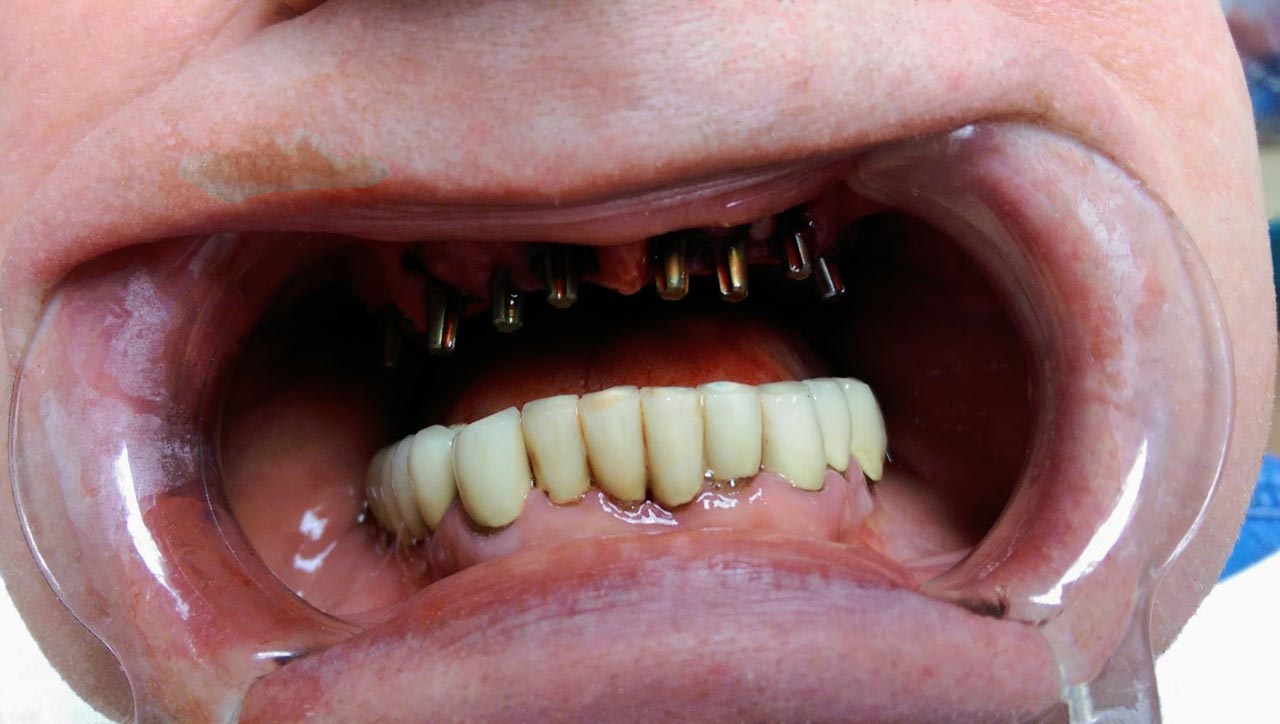

Műtét másnapján, implantátumok a szájban.

• esettanulmany-09

• esettanulmany-40